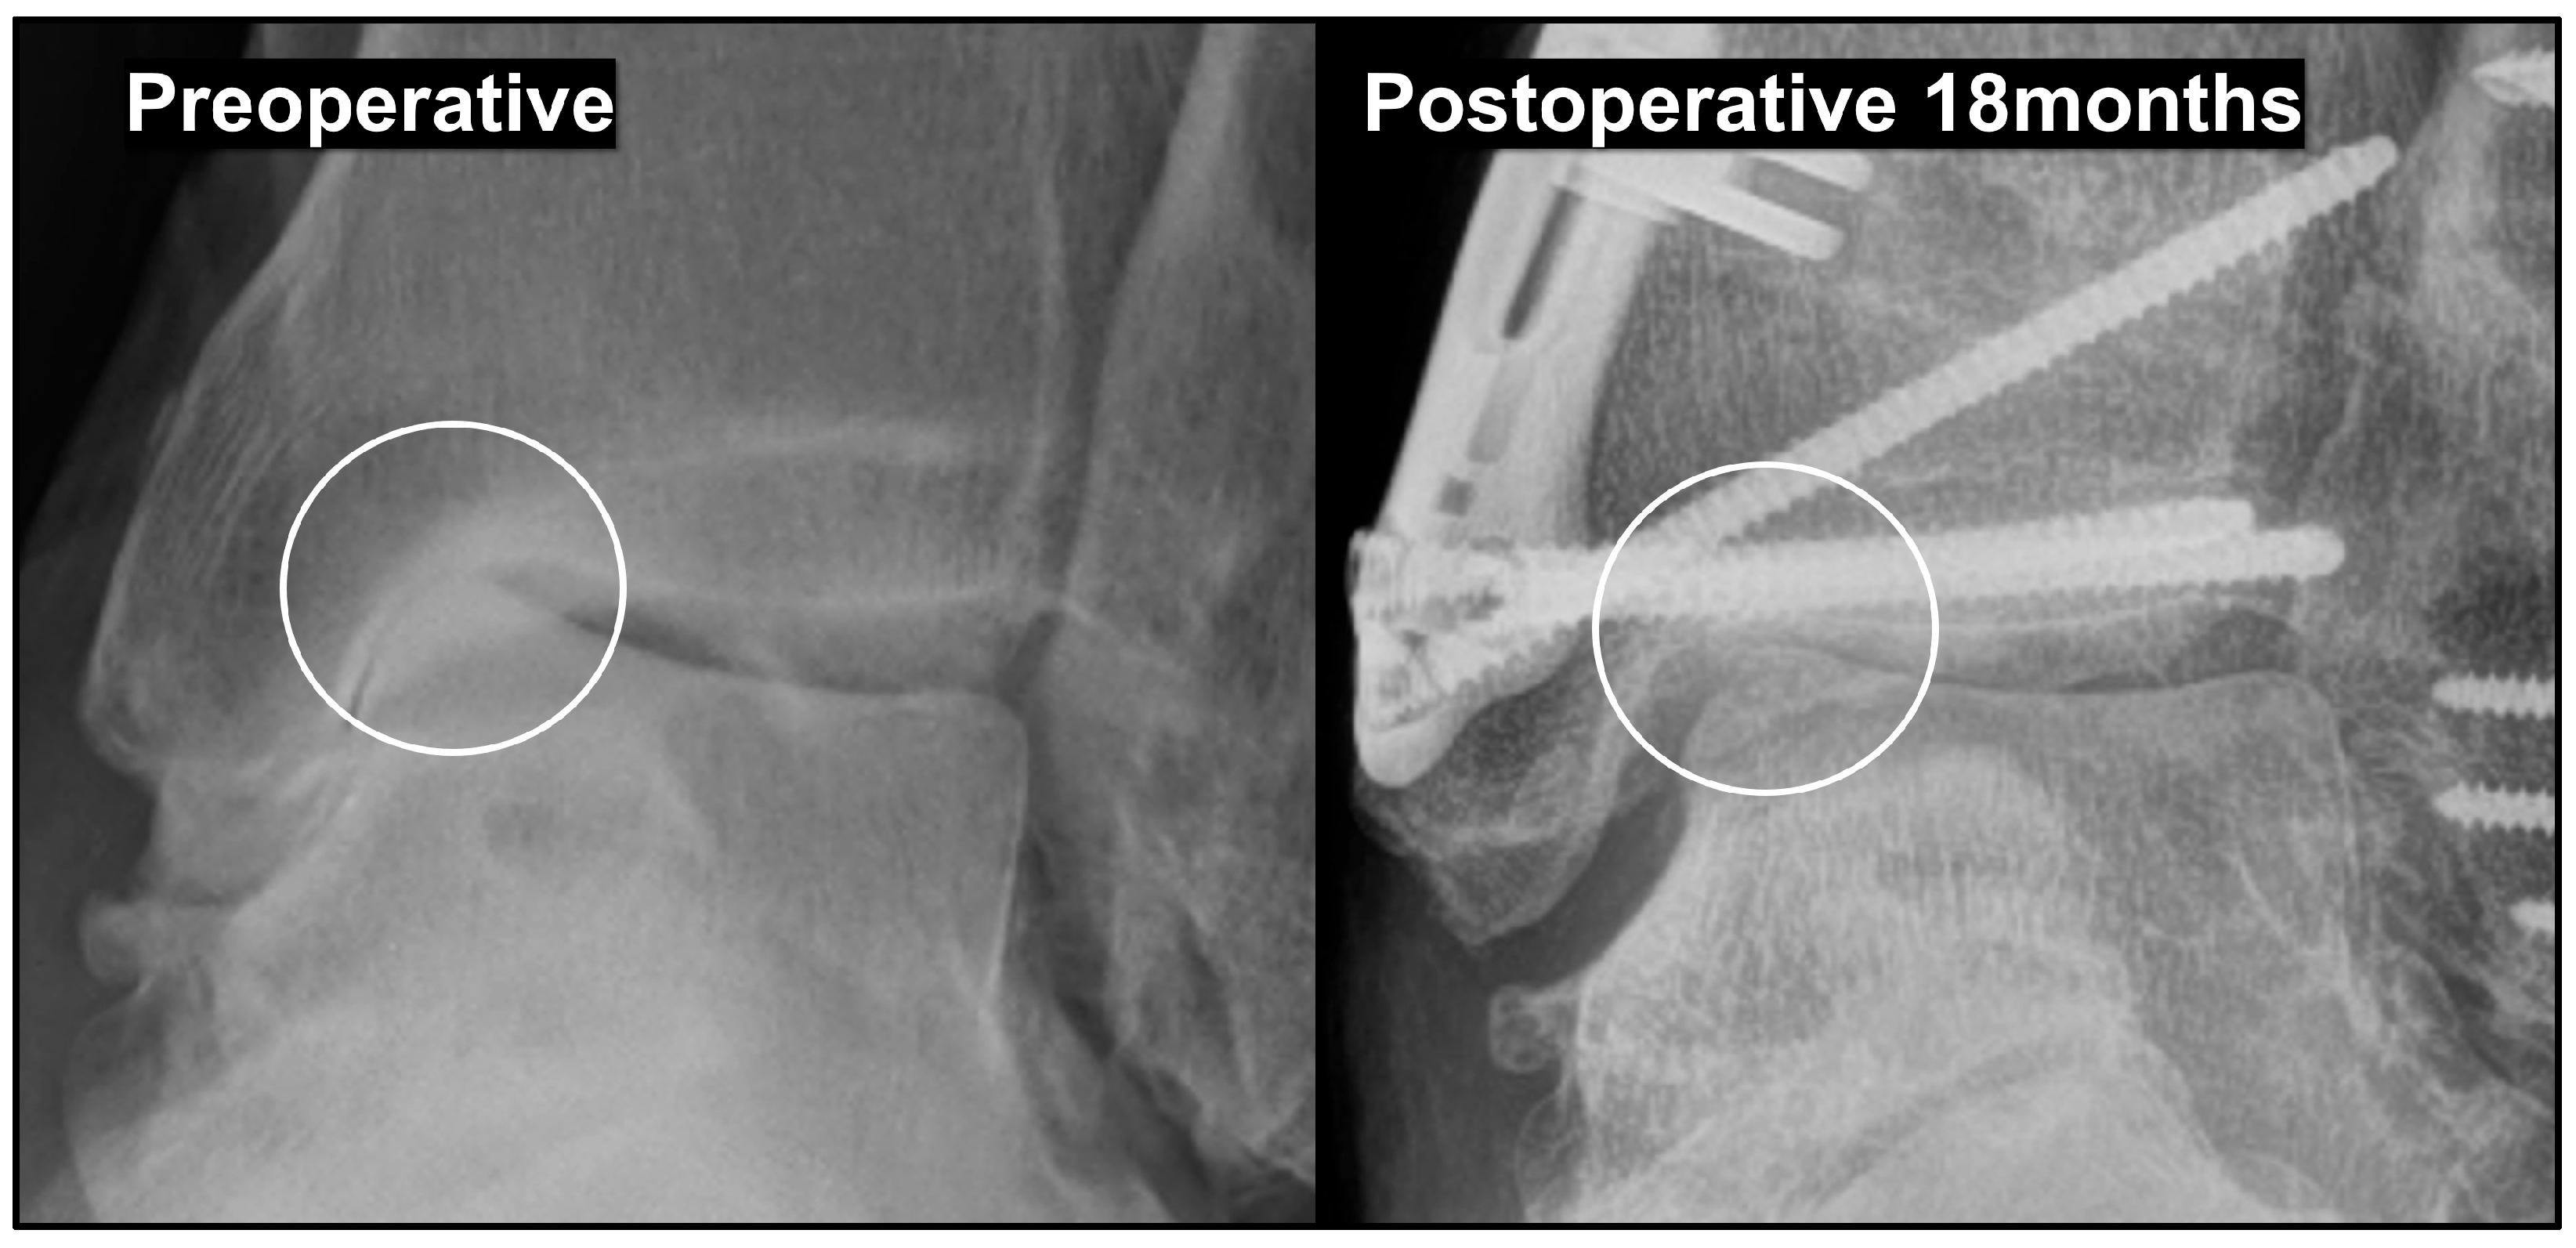

3.4. Effects and Prevention of Hinge Fracture

- Choi, J.Y.; Suh, J.S. Joint preserving procedures for Takakura stage IIIB varus ankle osteoarthritis. BMJ Case Rep. 2024, 17, e260585. [Google Scholar] [CrossRef]

- Choi, J.Y.; Suh, J.S.; Song, T.H. Protective Kirschner wire fixation to reduce the effect of lateral hinge fracture during the medial opening wedge low tibial osteotomy: A technical note. Tech. Orthop. 2024, 39, 17–19. [Google Scholar] [CrossRef]